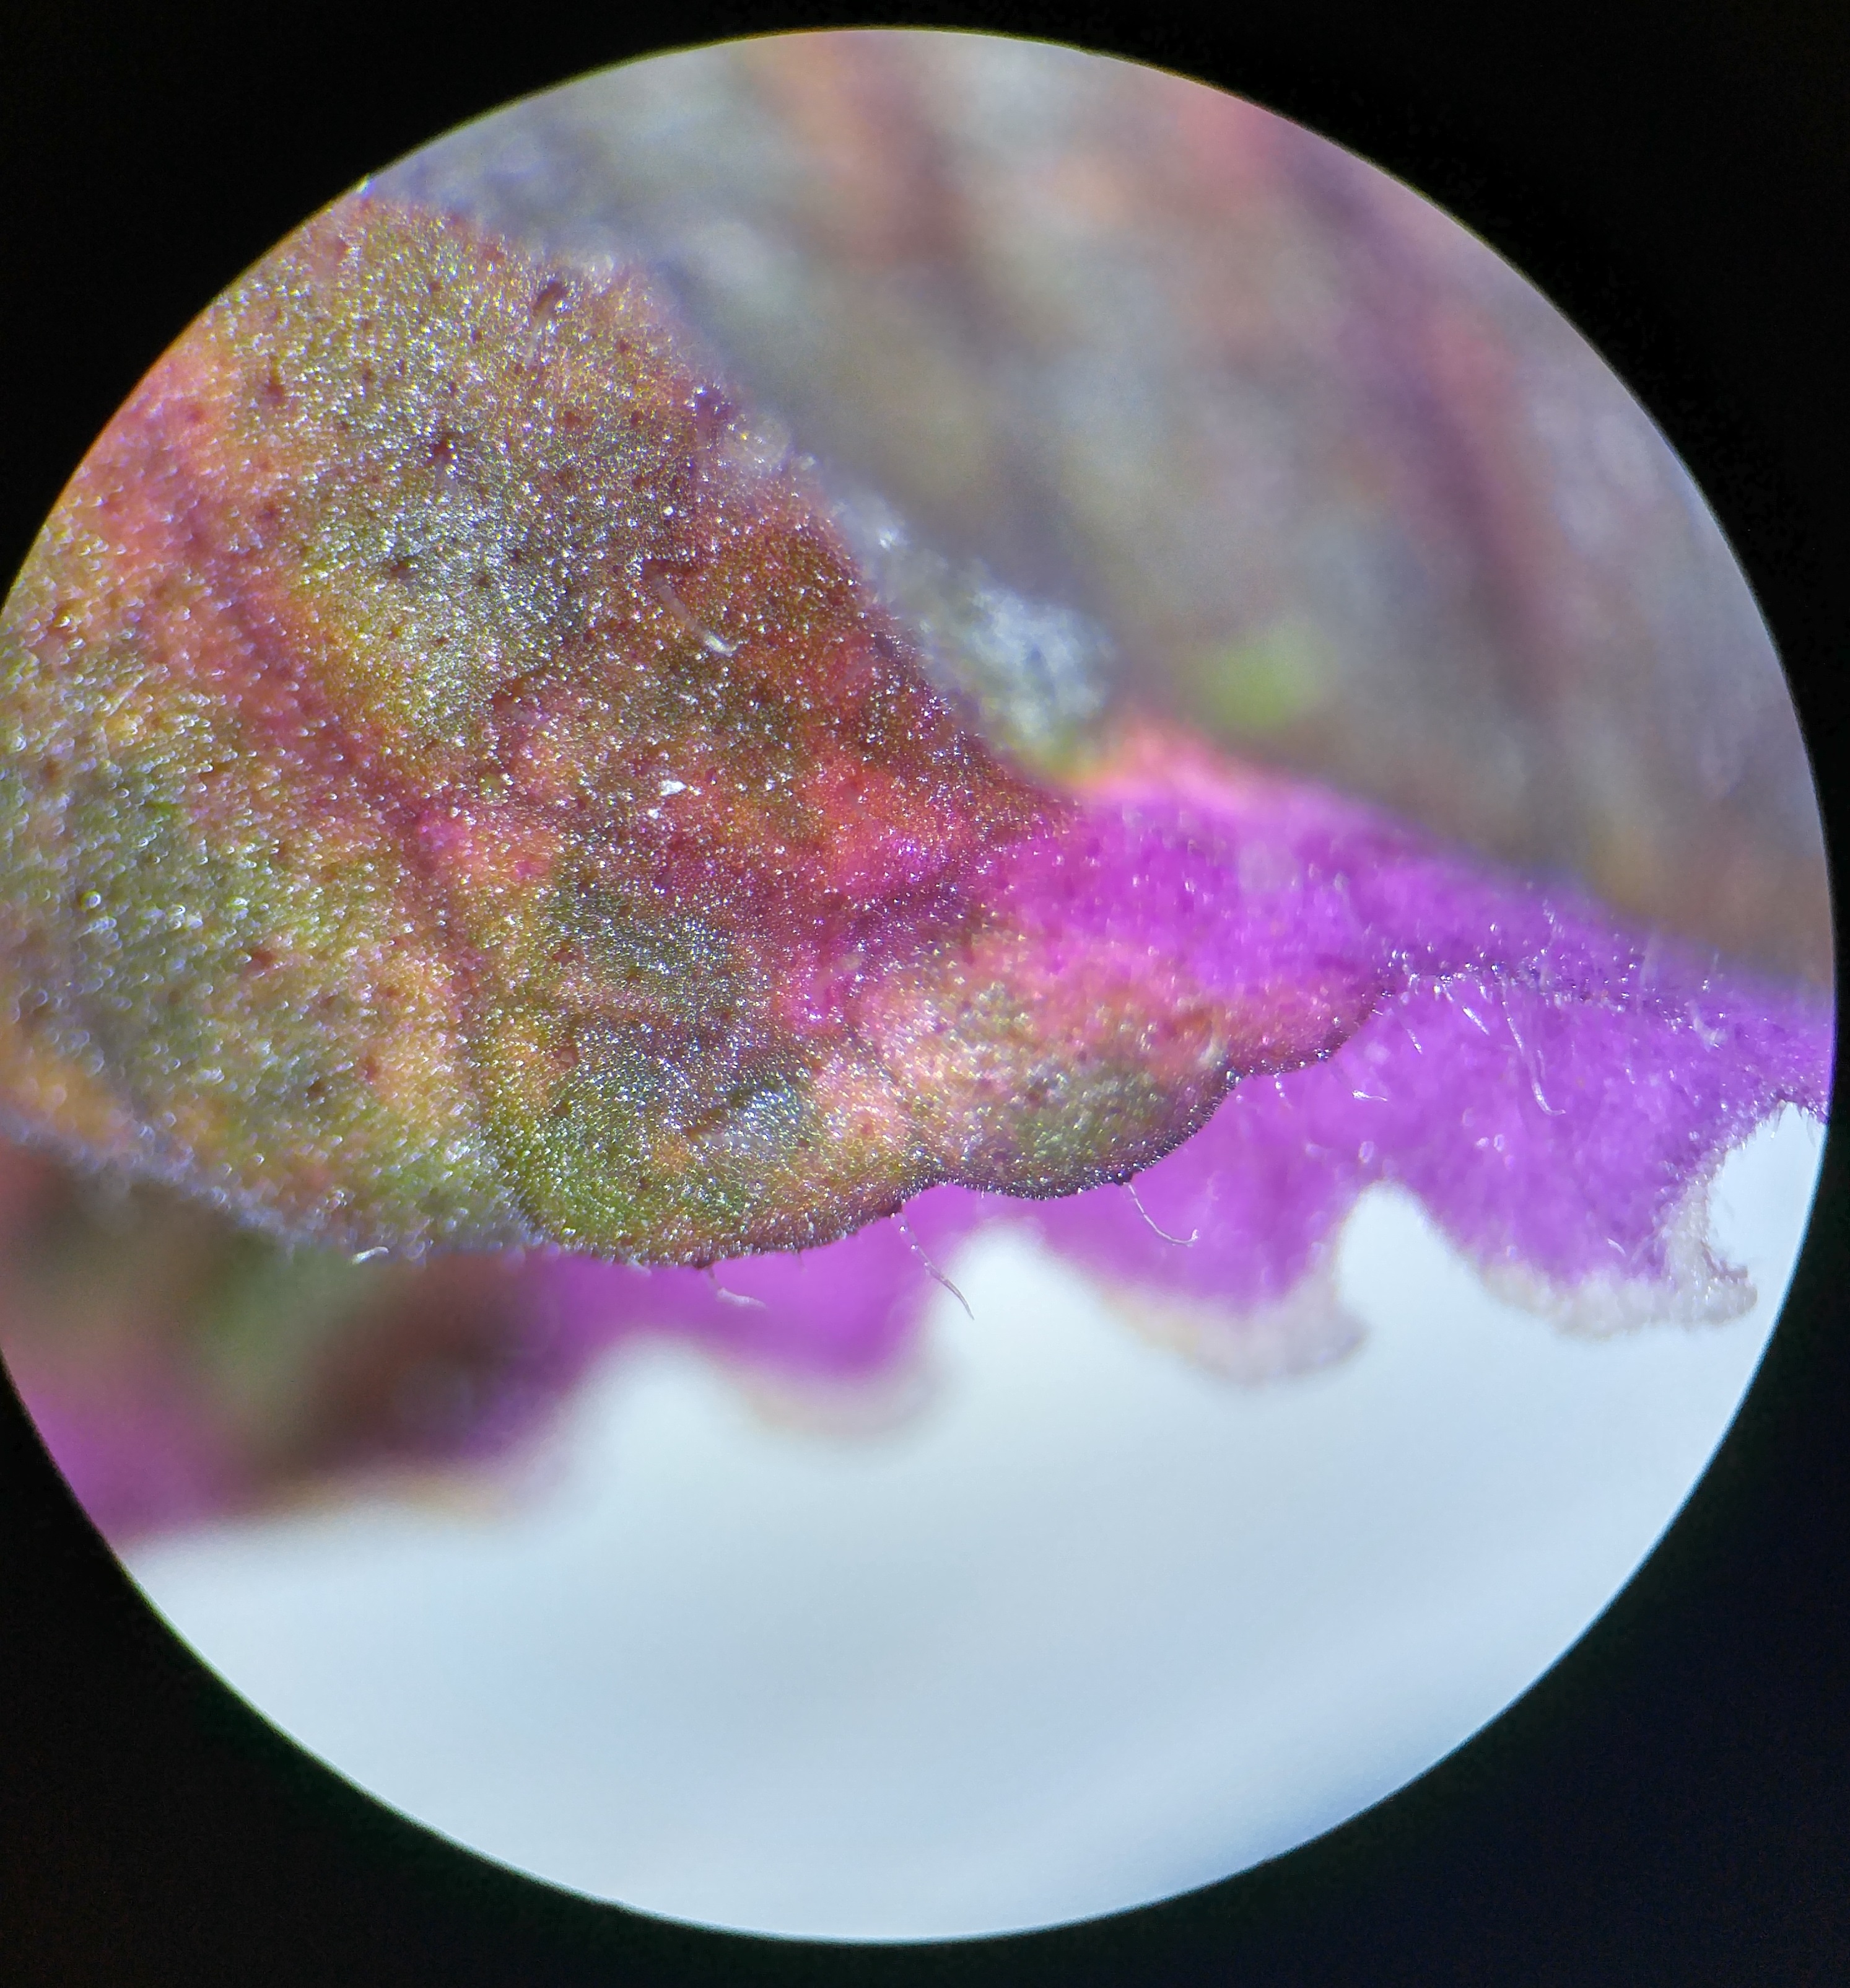

All Rights Reserved. Noah Zalev, 2017